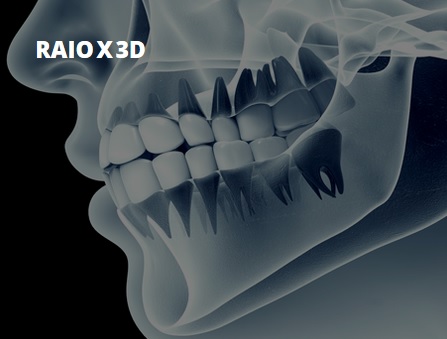

Raio X 3D A nossa clínica está preparada com o equipamento Raio X 3D que realiza ortopantomografias digitais e também tomografias axiais computadorizadas (TAC), o que torna o serviço de diagnóstico mais rápido e facilita o nosso serviço interno, estando também disponível para serviços externos. |